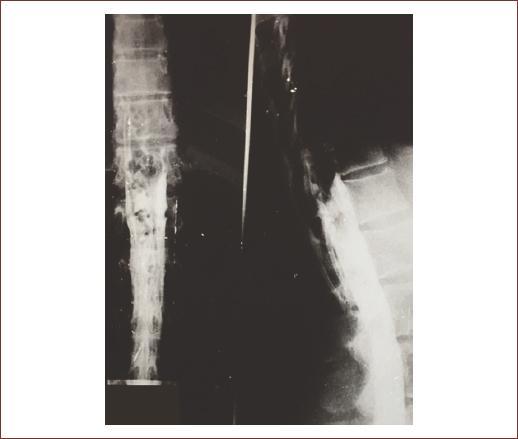

Imaging is an essential component in the diagnosis, management, and follow-up of patients with AVMs in the brain and spine. A wide variety of imaging modalities are available for its use, such as computed tomography (with its permutations: non-contrast, contrast enhanced, angiography perfusion, and myelography (Fig. 1) and magnetic resonance imaging (with its permutations: non-contrast, contrast enhanced, angiography, and myelography (Fig. 2). Although advances in this noninvasive imaging, digital subtraction angiography continues to be the gold standard for diagnosing and characterizing the detailed anatomic localization, arteriovenous transit, and venous drainage patterns of sAVMs29,33,38.